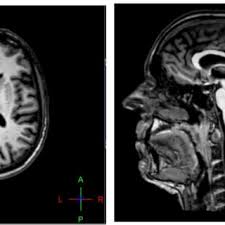

MRI 이미지의 값은 해당 위치의 이미지 강도를 나타낸다. sMRI의 경우 이 값은 해당 위치의 뇌 물 밀도를 효과적으로 나타냅니다. 이러한 값을 회색조에 색으로 표시하면 뇌의 구조를 볼 수 있다. 예를 들어, 다음은 뇌를 가로지르는 단면이다.